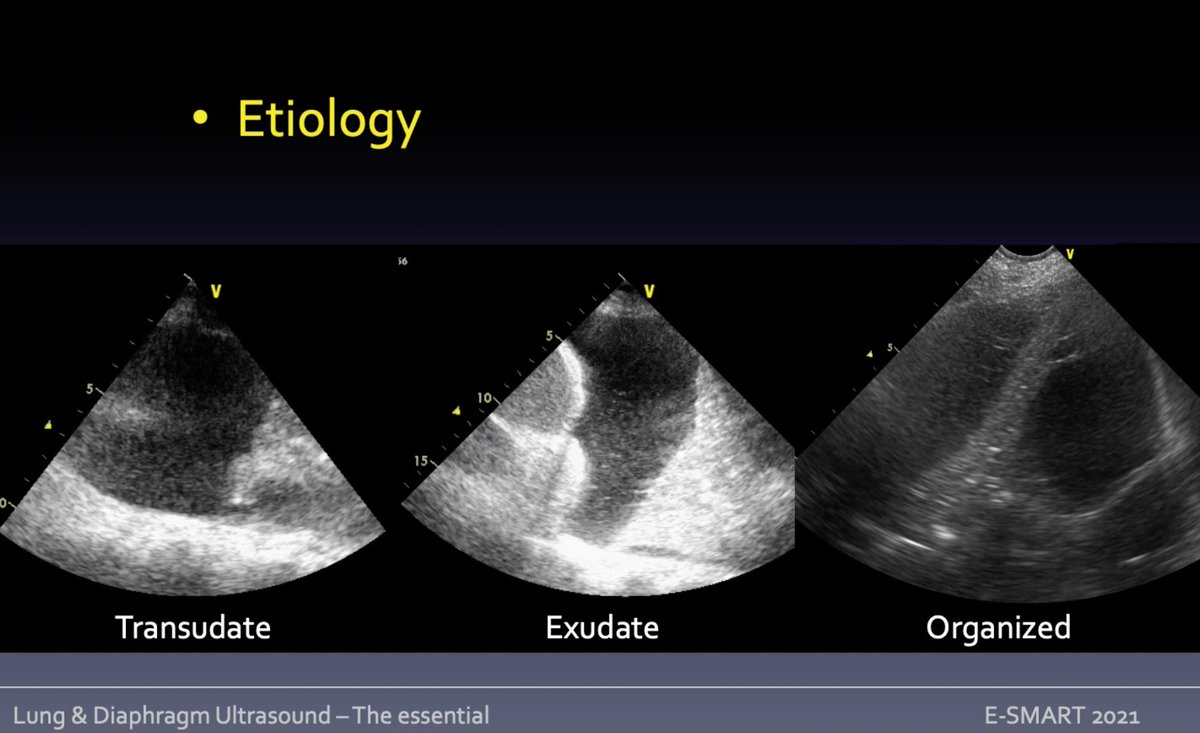

Pleural effusion = anechogenous space between pleuras. Is inside thorax? pleural vs abdominal fluid = aspect; curtain sign: aerated costophrenic recesses/peripheral bases.

➡️transudate: anechogenous/homogeneous

➡️SEC: inflammatory

➡️organized: septa

🧵Mongodi S #eSMART2021 #POCUS